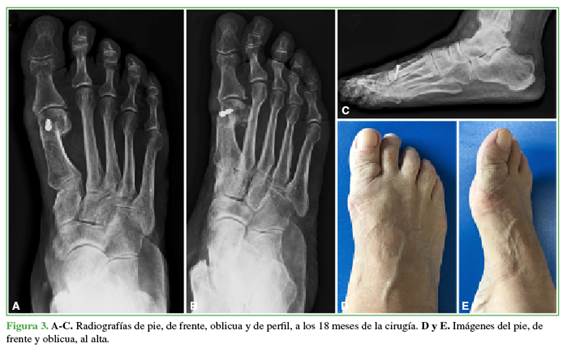

A todos los pacientes se les tomaron radiografías anteroposterior, latero-lateral con apoyo y oblicua de pie antes de la cirugía (Figura 1), en el posoperatorio (Figura 2) y a los 18 meses de la intervención (Figura 3) para establecer el ángulo intermetatarsiano (IM), el ángulo del hallux valgus (HV), el ángulo articular metatarsiano distal (AMD), la congruencia de la articulación metatarsofalángica, el ángulo interfalángico, la altura del M1, el grado de deformidad, el grado de lesión, la movilidad articular del hallux, la presencia de dolor, y para planificar la cirugía.

Se tomaron radiografías del pie de frente, oblicua y de perfil en el posoperatorio inmediato para evaluar una posible pérdida de la reducción. Se consideró un resultado radiográfico definitivo a los 18 meses o más de la cirugía.

Los ángulos del HV eran de 30,34° (rango 17-45) antes de la intervención; 1,60° (rango 0-9) en el posoperatorio y 3,17° (rango 2-9) en el momento del alta. El ángulo IM preoperatorio era de 13,43° (rango 7-16) y 6,56° (rango 3-12) en el posoperatorio y 6,56º (rango 3-12) al alta. Los ángulos AMD preoperatorio, posoperatorio y al alta fueron de 7,78° (rango 6-9), 7,17° (rango 6-9) y 7,17º (rango 6-9), respectivamente.

Luego de consolidada la osteotomía, se observó, en todos los casos, un desplazamiento lateral de la cabeza del M1 sin colapso ni pérdida de la reducción cuando se otorgó el alta.